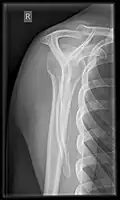

X-ray

Projectional radiography views of the shoulder include:

- Transaxillary projection

The arm should be abducted 80 to 100 degrees. This method reveals:[26]

- The horizontal alignment of the humerus head in respect to the socket and the lateral clavicle in respect to the acromion

- Lesions of the anterior and posterior socket border, or of the tuberculum minus

- The eventual non-closure of the acromial apophysis

- The coraco-humeral interval

Transaxillary conventional radiography -